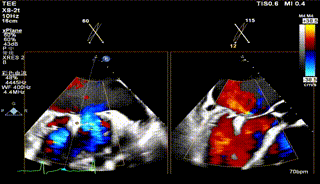

术前TEE评估

术前瓣膜介入团队的心超医生陈星星医师王良国医师对患者的心脏结构和瓣膜解剖情况进行详细的评估:

1.二尖瓣重度关闭不全(4+),瓣环明显扩大(AP径4.6cm,LM径3.9cm),扁平,关闭时瓣叶对合不佳(carpentier I),1-3区均可见反流束,返流宽度达26mm;肺静脉频谱呈收缩期反向。

2.画迹法测得二尖瓣瓣口面积约8.8cm²。

3.PISA法测得EROA=0.57cm²,Rvol=77ml,r=11mm。

4.二尖瓣前叶(A2)长度29mm,后叶(P2)长度11mm。

5.左房巨大(三径86*84*114mm),右房巨大(内径114*86mm),CFI提示极重度三尖瓣反流,Teich法测得EF为70.1%。

2区

2区带彩

3区

3区带彩